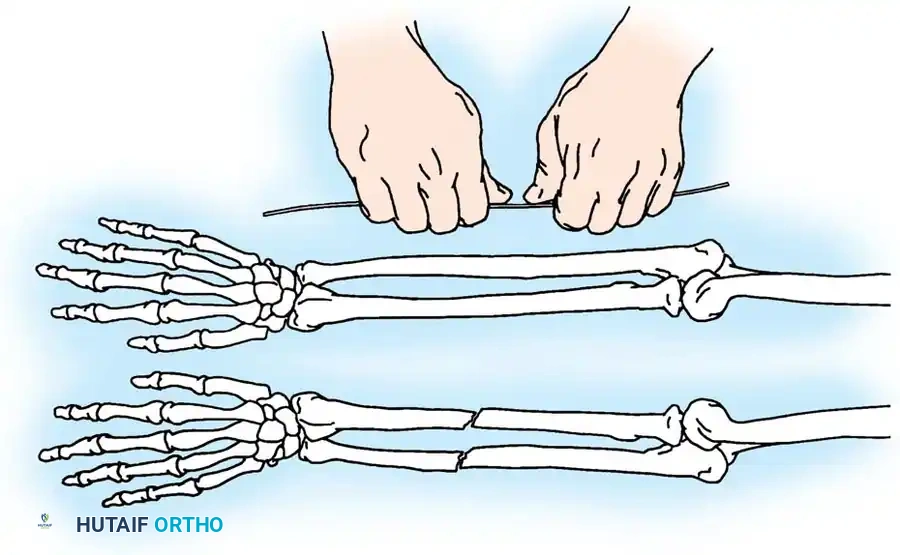

RADIUS AND ULNA: OPERATIVE PRINCIPLES

Fractures of the forearm bones in adults frequently demand surgical intervention to restore the complex biomechanics of the upper extremity. Surgical indications encompass fractures of the olecranon, the head or neck of the radius, and the proximal third of the ulna associated with dislocation of the radial head (Monteggia lesions). Furthermore, operative management is routinely indicated for isolated displaced fractures of the ulnar or radial shafts, as well as diaphyseal fractures involving both bones.

The primary goal of surgical intervention in the forearm and elbow is the exact restoration of anatomical alignment, axial length, and rotational stability. In the proximal ulna, the olecranon forms the greater sigmoid notch, articulating with the trochlea of the humerus. Any disruption here not only compromises the extensor mechanism but also threatens the intrinsic stability of the elbow joint.

2. Intramedullary Fixation with Tension Band

If the fracture is more distal, or if there is a tendency for the proximal fragment to angulate posteriorly, a simple tension band wire is insufficiently stable. In these cases, intramedullary fixation (using Kirschner wires or a large cancellous screw) is combined with the tension band.

Kirschner Wires vs. Cancellous Screws:

* K-wires: The AO technique utilizes two parallel K-wires (1.6 mm or 2.0 mm) driven down the medullary canal. To prevent proximal migration, the K-wires must engage the anterior cortex of the ulna distal to the coronoid.

* Cancellous Screw: A biomechanical analysis by Murphy et al. demonstrated that a long 6.5-mm or 7.3-mm AO cancellous screw combined with a figure-of-eight wire provides a significantly stronger construct than K-wires. The screw must be long enough to achieve secure purchase in the ulnar diaphysis.

Fig. 54-55 Olecranon fracture repaired with long 6.5-mm AO cancellous screw and figure-of-eight tension band wire loop. Screw must engage cortex of diaphysis of ulna.

🔪 Surgical Technique: K-Wire and Tension Band (AO Technique)

- Reduction: Anatomically reduce the fragments and hold them temporarily with a reduction clamp.

- K-Wire Insertion: Introduce two parallel K-wires longitudinally from the tip of the olecranon across the fracture site. Direct them slightly anteriorly so they engage the anterior ulnar cortex distal to the coronoid process.

- Wire Loop: Pass an 18-gauge wire through a transverse drill hole in the distal fragment. Cross the wire in a figure-of-eight fashion over the posterior surface.

- Proximal Capture: Pass the wire around the protruding proximal ends of the K-wires.

- Double Twist: Weber and Vasey suggest twisting both limbs of the figure-of-eight loop. This double-twist modification ensures uniform compression across the fracture site.

- Securing K-wires: Bend the proximal ends of the K-wires 180 degrees, cut them short, and tap the bent ends deep into the triceps insertion and proximal bone to prevent symptomatic hardware prominence and migration.

Fig. 54-56 A and B, Transverse olecranon fracture repaired with Kirschner wires and tension band technique. C, Double twist modification of wiring suggested by Weber and Vasey.